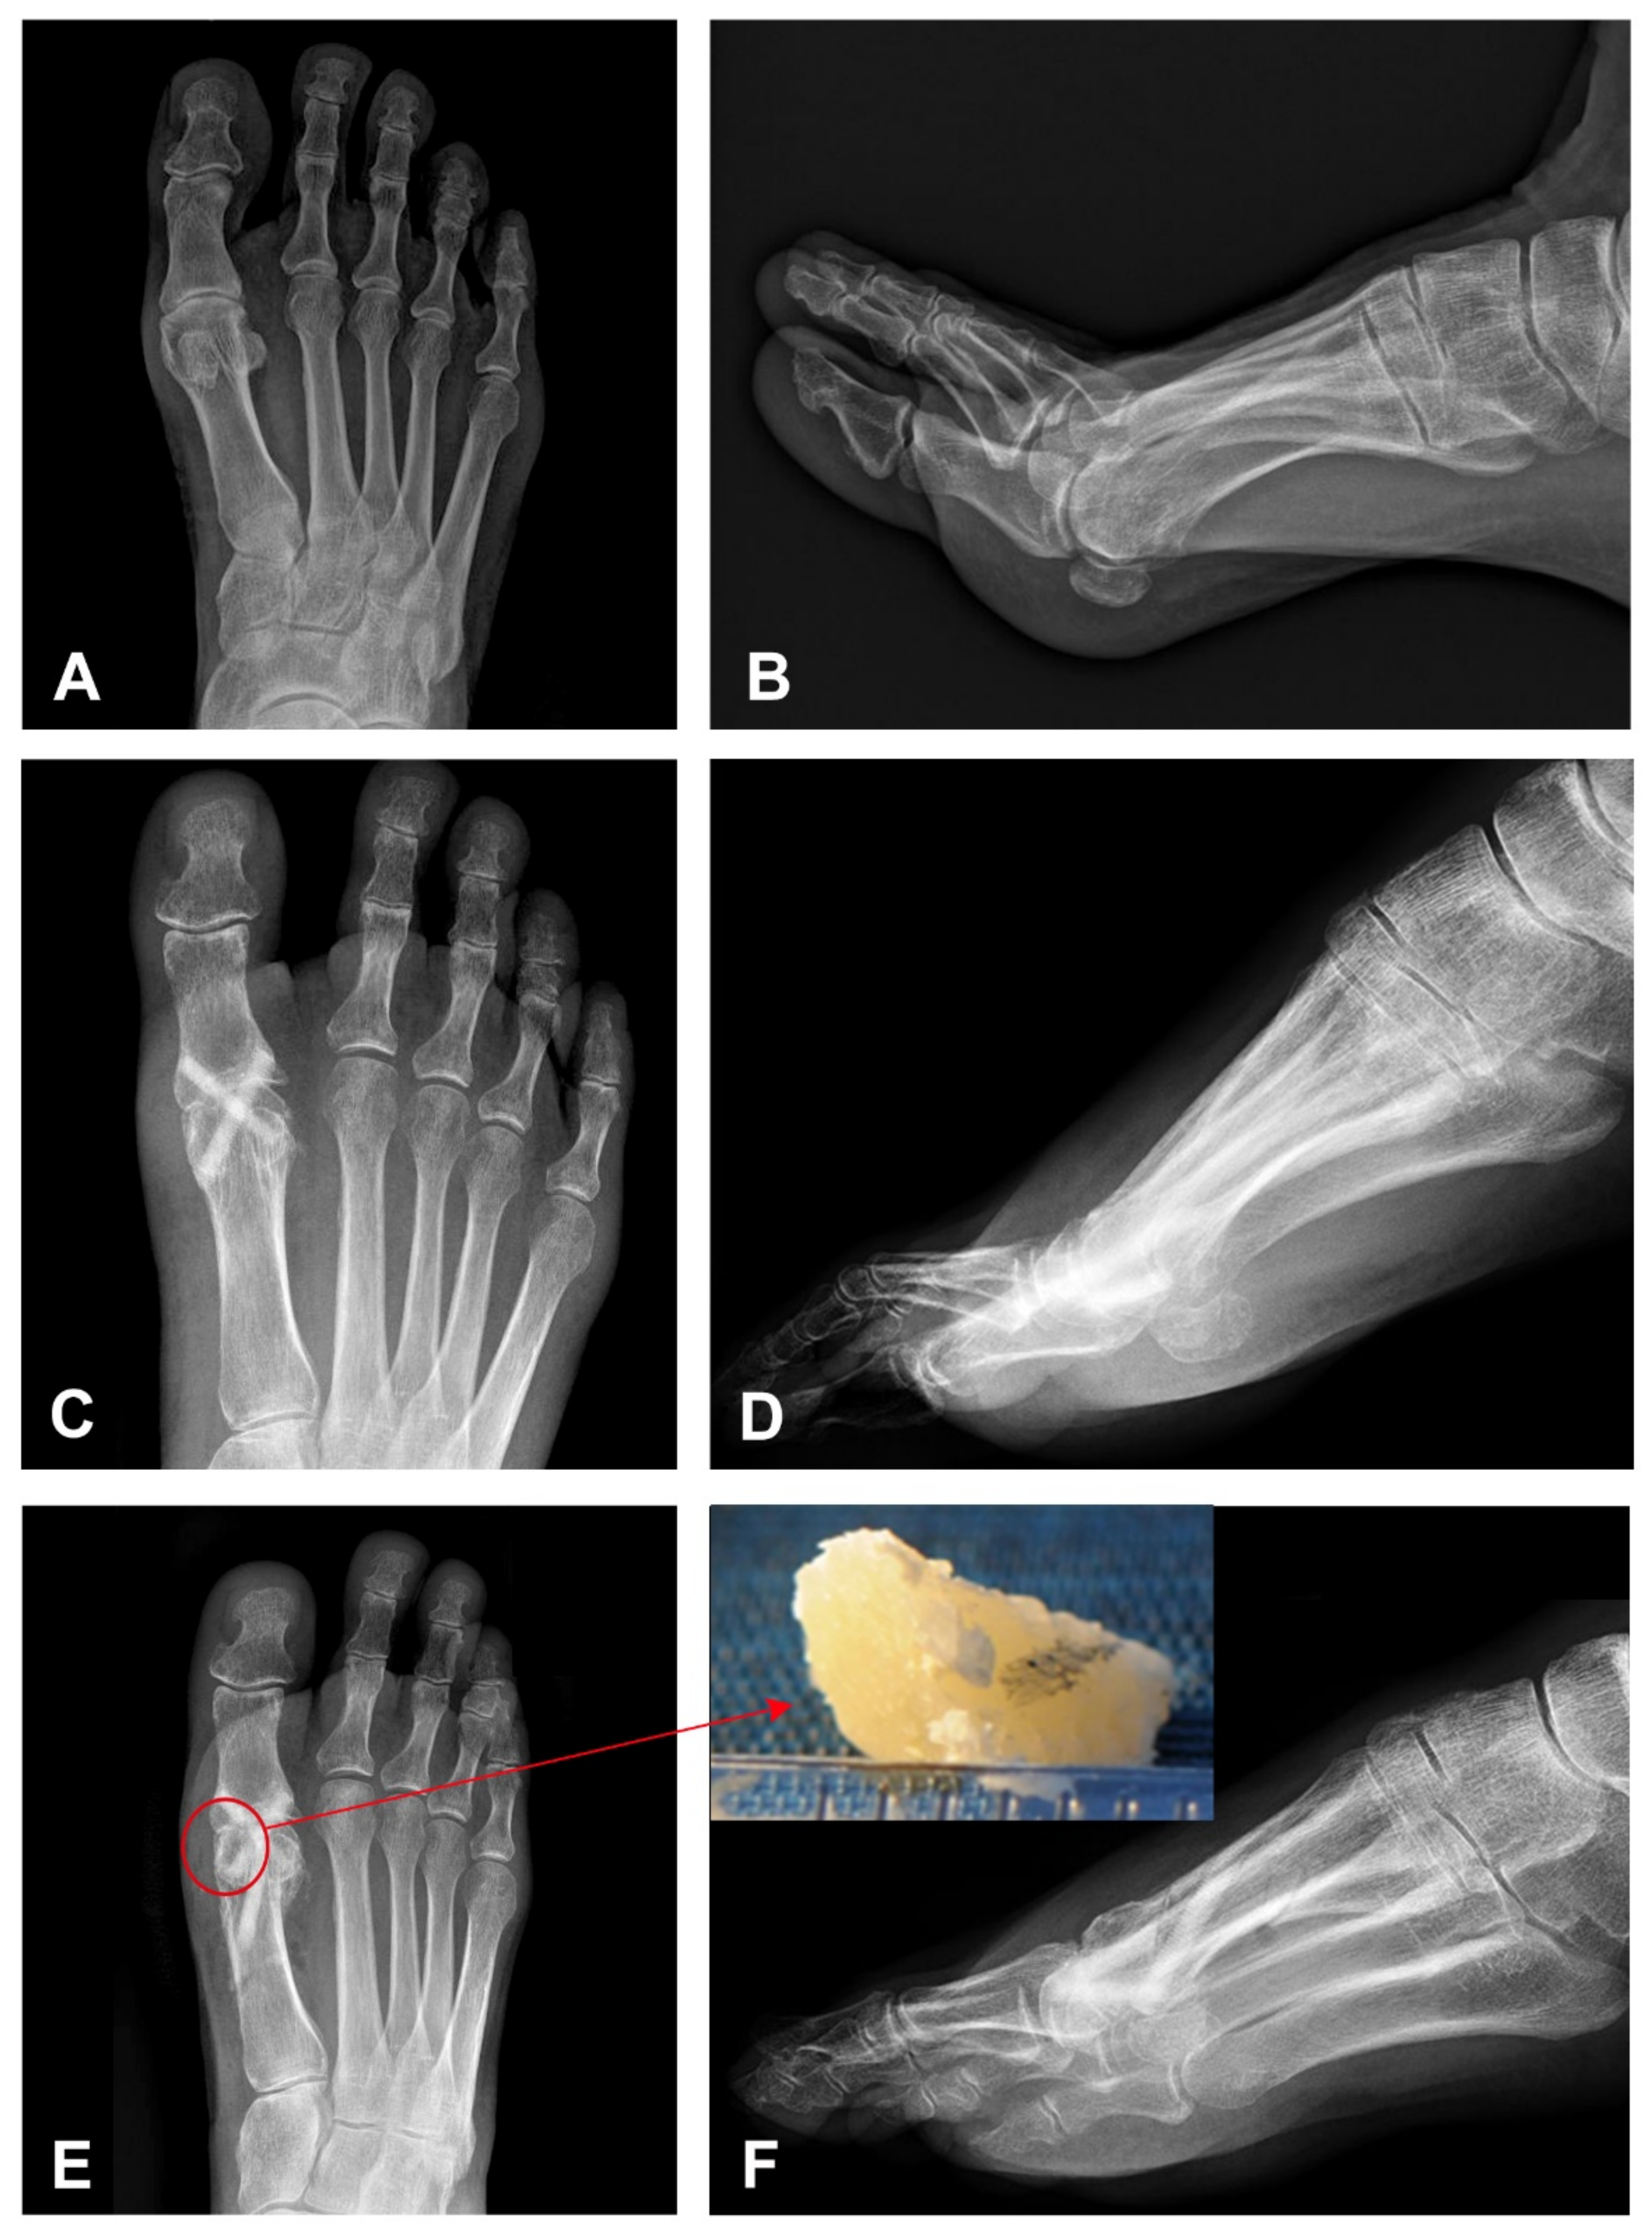

3. Case Presentation